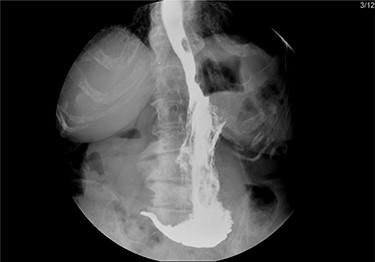

After mobilization of the left liver lobe, visualization of the hiatus was achieved. A two silk suture was placed through the avascular hepatogastric ligament and outside the patient’s anterior abdomen with an extracorporeal knot in order to assure atraumatic elevation-retraction of the liver. Space was created in the surgical field due to the absence of a retracting surgical instrument within the abdominal cavity. The hernia’s sac was then dissected with use of energy device and bipolar cautery with minimal traumatic tissue handling; the herniated stomach, transverse and left colon, omentum and finally spleen were dissected free (Fig. 2). Due to the atypical clinical symptomatology as well as increased PLT, the suspicion of chronic ischemia of the herniated organs was raised. ICG was administered to assess the patency of blood supply in the herniated organs and specially to the spleen; blood supply was excellent and as a result, no further resections were needed (Fig. 3). An 8- × 4-cm posterolateral diaphragmatic defect was revealed; the defect was repaired with the use of ProGrip mesh and was supported by a continuous V-loc suture for fixation. The patient resuscitated from anesthesia in great condition and returned to the ward, with an uneventful course. A post-operative upper GI fluoroscopy was conducted at the second post-operative day (POD), and oral diet was commenced (Fig. 4).

Upper GI fluoroscopy to assess the results of the hernia repair during the third POD.